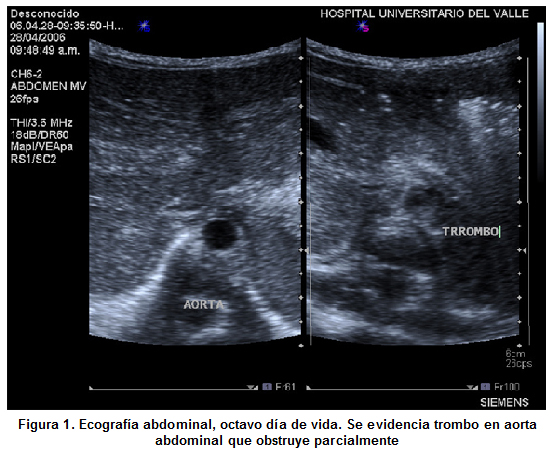

Se hospitalizó en la Unidad de Recién Nacidos (CIRENA) del Hospital Universitario del Valle (HUV), un recién nacido de género másculino, pretérmino de 34 semanas, con peso 2,035 g, con signos de dificultad respiratoria por lo que se realizó cateterismo umbilical venoso y arterial. Al cuarto día de vida presenta cifras tensionales elevadas y al séptimo día se evidencia acrocianosis, ausencia de pulsos y no detección de tensión arterial en miembros inferiores. Al octavo día de vida se retiran catéteres umbilicales, persiste hipertenso y con cambios descritos en miembros inferiores. Se realiza ecocardiograma observado trombo a nivel de arteria aorta. En su noveno día de vida se confirmó el diagnóstico por medio de ecografia Doppler (Figuras 1 y 2) donde se evidenció trombo que compromete parcialmente la arteria aorta y totalmente la arteria renal izquierda sin observarse flujo sanguíneo en riñón izquierdo.